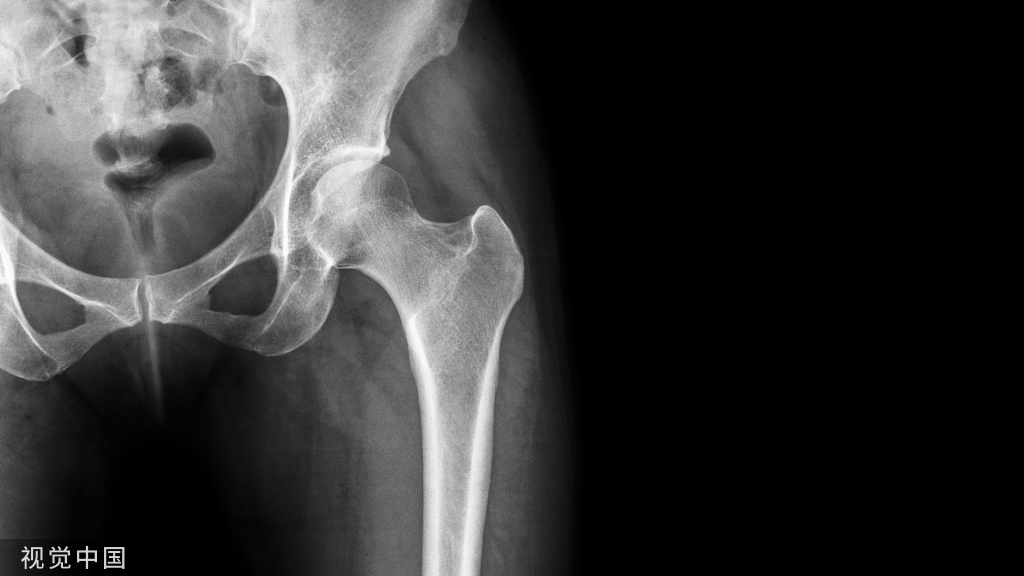

29、股骨颈正常透亮区

• 股骨颈正常透亮区,又叫Ward,s三角形。